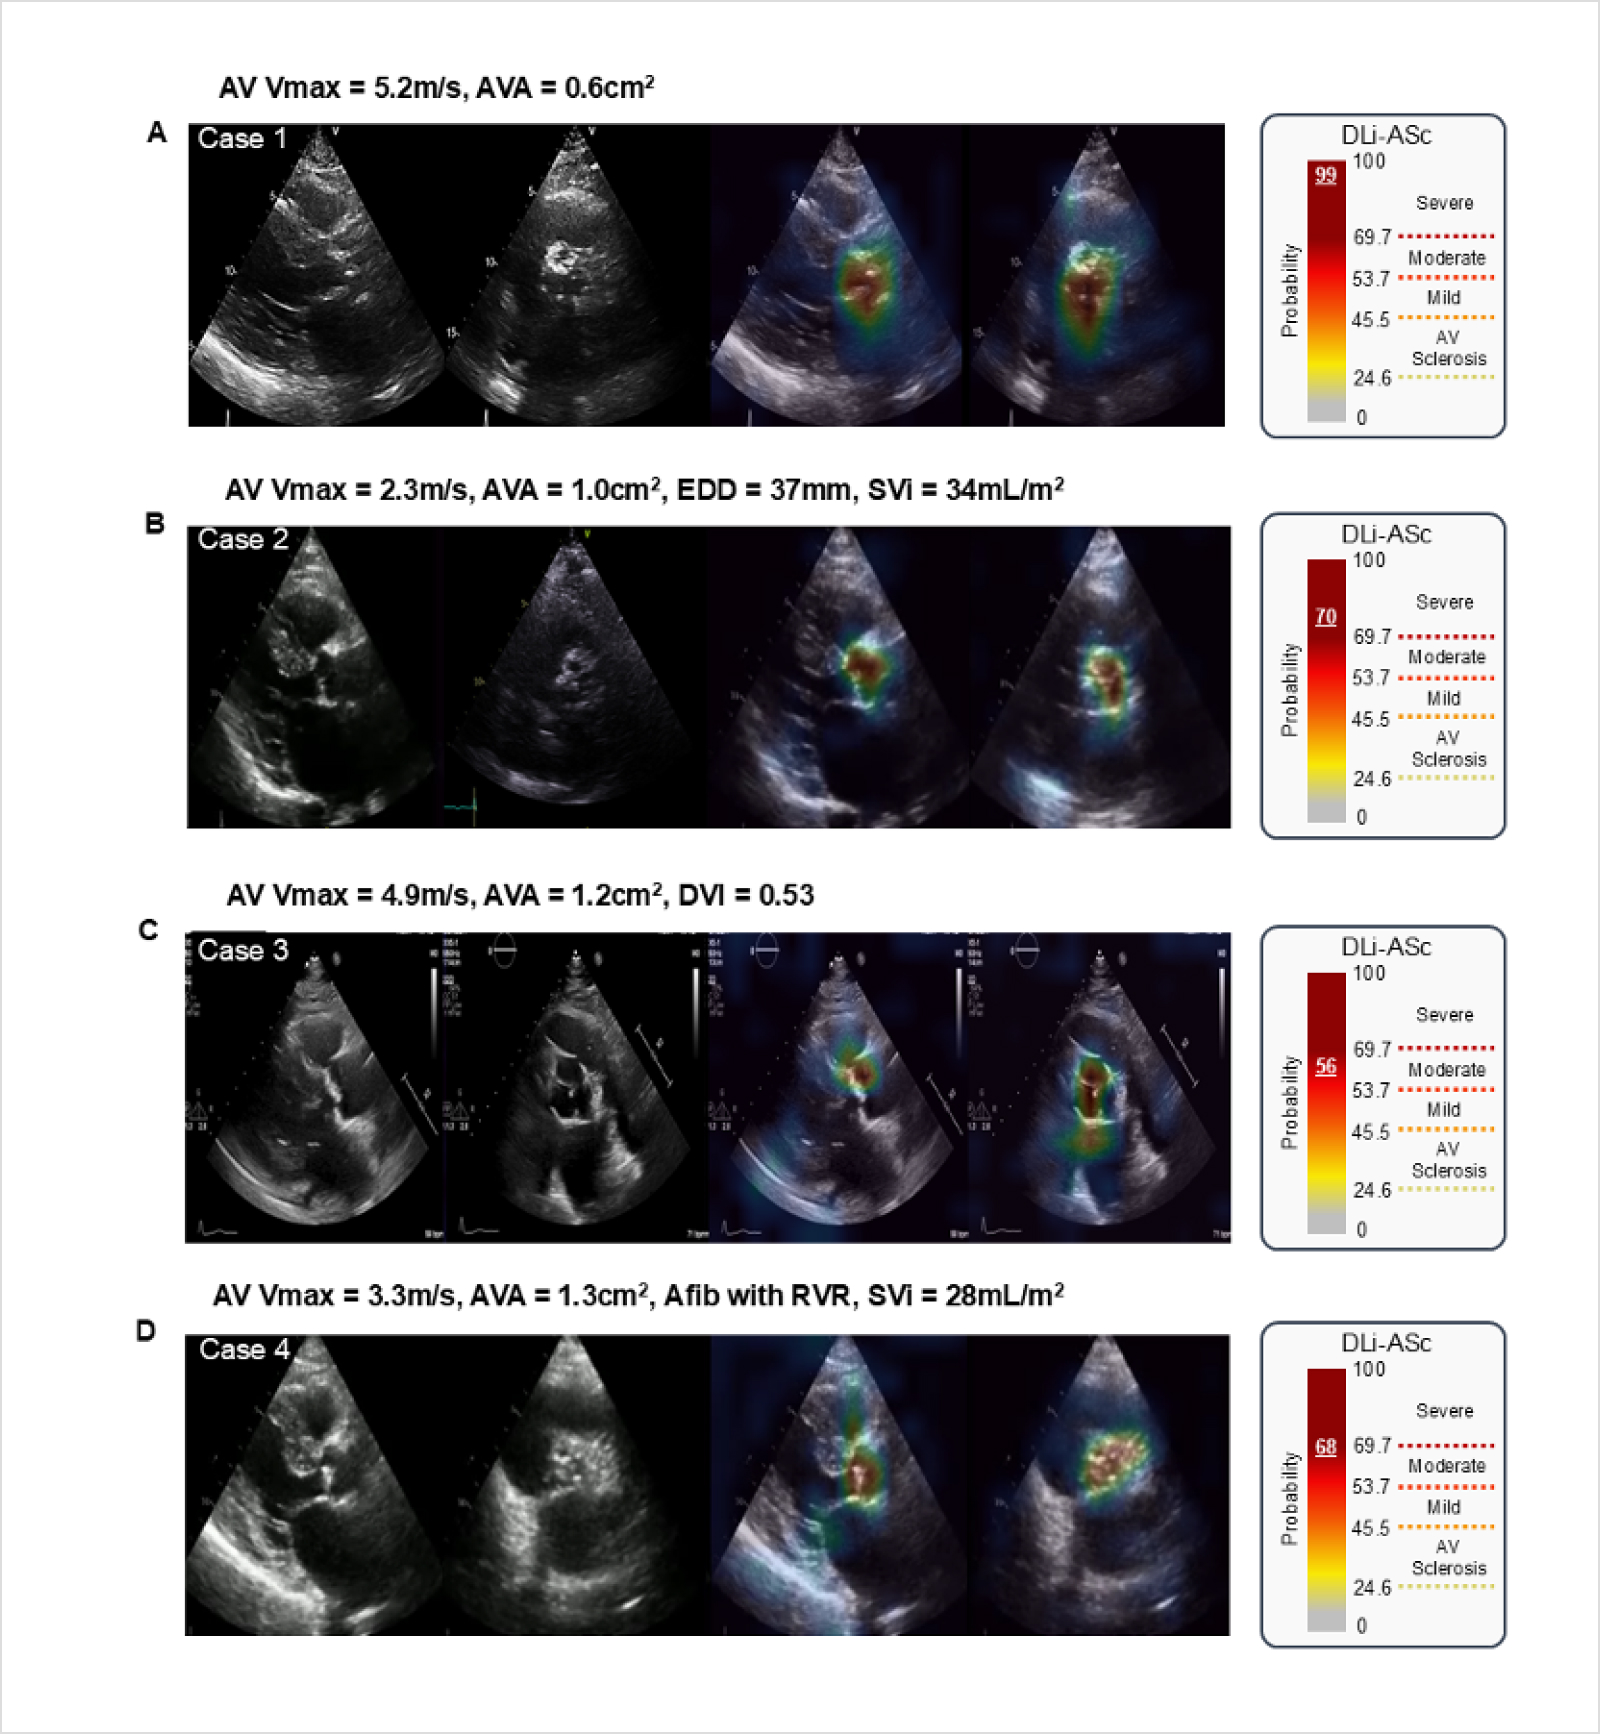

특히, 본 연구에서는 △전통적인 검사와 일치하는 중증 AS 사례, △비전형적인 저유량·저구배 AS 사례, △좌심실 유출로 폐색 (LVOT obstruction)으로 인해 과대 평가된 사례, △심방세동으로 인해 중증도가 과소 평가된 사례 등 다양한 상황에서 DLi-ASc가 어떻게 유용하게 활용될 수 있는지를 구체적인 사례를 통해 보여주었습니다.

(A) 전통적인 도플러 지표와 DLi-ASc 모두 severe AS를 일치하게 진단한 경우.

(B) Paradoxical LFLG AS로 전통적인 도플러 평가에 근거하여 moderate AS로 진단되었으나, DLi-ASc는 중증에 근접한 값을 보여 임상적 재평가가 필요한 경우.

(C) 좌심실 유출로 폐색 (LVOT Obstruction)으로 도플러 속도는 높았지만, 실제로는 moderate AS였던 경우. DLi-ASc 역시 중등도로 평가되어 과진단을 방지하는 데 도움을 줄 수 있음.

(D) 심방세동 (AF)과 빈맥 상태에서 전통적인 평가로는 moderate AS였으나, DLi-ASc는 중증 경계 값에 근접하여 주의가 필요하였으며, 동율동으로 전환 후 severe AS로 확인된 사례.